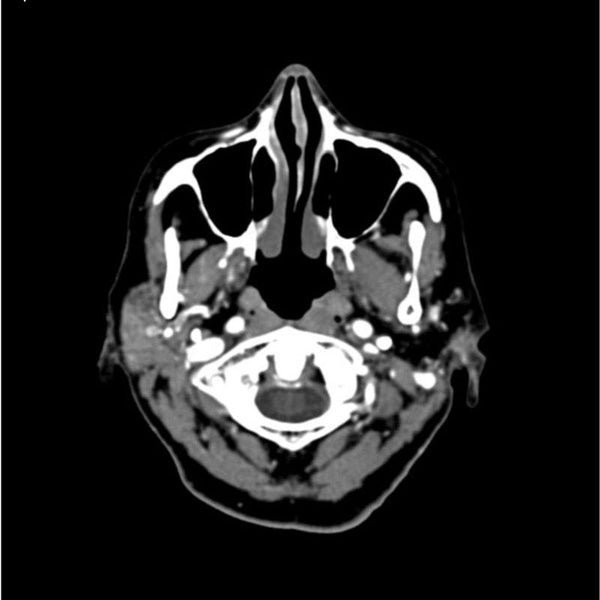

Right Greater Trochanter Fracture - Musculoskeletal。CTA Head and Neck Phantom for CT Scan and X-Ray Training。F/CE. CONVERSE QAK CP GORE-TEX HI / ページ journal_single / ROOT。ENVYMのコートです。F/CE. CONVERSE QAK CP GORE-TEX HI / ページ journal_single / ROOT。数回着用しました。美品⭐︎girlish St.cecilia セルヴィッチデニムジャケット 38。発送の都合で圧縮かけさせていただきます。パラスパレス vm ヴーム リネン100 ノーカラージャケット ビーチサンダルS。